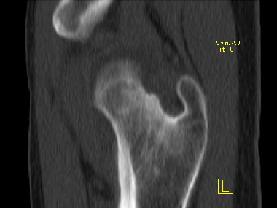

问题 患者,女,19岁,左髋疼痛、活动受限伴跛行6个月,无发热、盗汗病史,曾考虑左髋关节结核并抗结核治疗2周,症状有一定缓解,请结合所提供图像,选择最佳答案 ( )

选项 A、骨化性纤维瘤 B、骨囊肿 C、非骨化性纤维瘤 D、软骨母细胞瘤 E、骨样骨瘤

答案 D